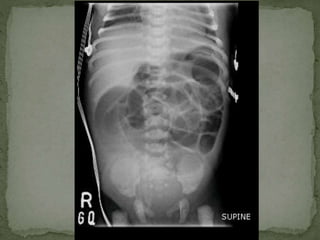

 Abdominal X ray 16th June, 2013

 Dilated bowel loops

 No air in the rectum

 Multiple air fluid levels

 Abdominal Xray 16th June, 2013  Dilated bowel loops  No air in the rectum  Multiple air fluid levels